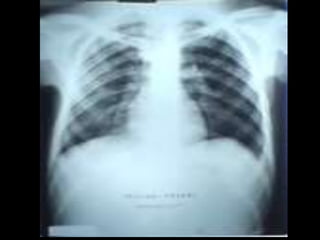

•   C’est un téléthorax de face objectivant une volumineuse opacité de

tonalité hydrique hilaire gauche Forme : grossièrement ovalaire

•   Taille : mesure 6 à 8 cm de grand axe

•   Limites : interne noyée dans le médiastin et se raccordant à angle aigue

avec le bord gauche du médiastin.

•   Limite externe flou irrégulière réalisant l’aspect en patte de crabe

•   Plage : hétérogène par la présence de broncho gramme aérien

•   Index cardio thoracique, les culs de sacs pleuraux sont libres

•   On note une petite opacité de tonalité calcique se projetant sur le lobe

supérieur du poumon droit

•   Conclusion : gros hile tumorale malin gauche évoquant un cancer

bronchique proximal

•   Pas de diagnostic différentiel

•   CAT : bilan d’extension:fibroscopie bronchique, TDM thoraco-

abdominale, échographie abdomino-pelvienne et scintigraphie osseuse